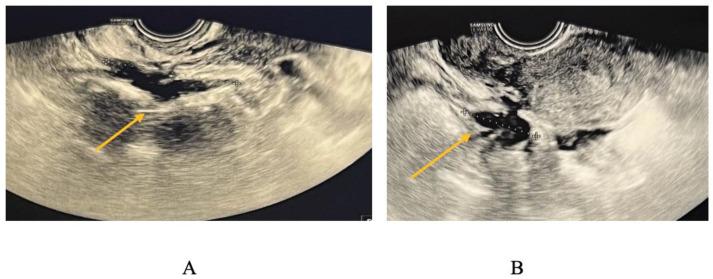

经阴道超声与磁共振成像:诊断子宫内膜异位症的最佳成像方式是什么?

Transvaginal Ultrasound vs. Magnetic Resonance Imaging: What Is the Optimal Imaging Modality for the Diagnosis of Endometriosis?

Endometriosis, an intriguing gynecological illness, poses a substantial health concern for women of reproductive age, despite its widespread occurrence and limited comprehension. The objective of this study is to assess the diagnostic precision of transvaginal sonography (TVS) and pelvic magnetic resonance imaging (MRI) for the identification of deep infiltrated endometriosis (DIE). This study encompassed a cohort of 256 patients exhibiting signs and symptoms of endometriosis, with the aim of assessing the diagnostic accuracy over a span of four years. Both TVS and pelvic MRI were employed in the same centers to analyze each subject. The histopathologic analysis and laparoscopy were the most reliable and widely accepted methods for evaluation. TVS is a reliable diagnostic tool for ovarian endometriomas, obviating the necessity for MRI confirmation. The specificity of TVS in diagnosing ovarian endometriomas is 57.14%, while its sensitivity is 93.78%, resulting in an overall accuracy of 84.47%. In relation to parametrial lesions, the sensitivity, specificity, and accuracy of TVS and MRI were as follows: TVS: 9%, 97%, 32%, MRI: 27.14%, 89.19%, and 40.11%. Concerning the uterosacral lesions, the sensitivity, specificity, and accuracy of TVS and MRI were as follows: TVS:14.63%, 94.74%, and 55%, while MRI: 65.88%, 66.30%, and 66.1%. Regarding rectal endometriosis, the sensitivity, specificity, and accuracy of TVS and MRI were as follows: 69.72%, 76.87%, and 73.82% for TVS, and 66.28%, 94.51%, and 80.79% for MRI. The results of the present study indicate that whereas MRI generally exhibits superior capability in assessing the severity of endometriosis, TVS demonstrates sufficient diagnostic accuracy in DIE comparable to MRI.

摘要

子宫内膜异位症是一种引人关注的妇科疾病,尽管其发病率很高且人们对它的了解有限,但它对育龄女性的健康构成了重大威胁。本研究的目的是评估经阴道超声检查(TVS)和盆腔磁共振成像(MRI)对深部浸润性子宫内膜异位症(DIE)的诊断准确性。本研究纳入了256名有子宫内膜异位症体征和症状的患者,旨在评估四年间的诊断准确性。在同一中心对每位受试者同时采用TVS和盆腔MRI进行分析。组织病理学分析和腹腔镜检查是评估最可靠且被广泛接受的方法。TVS是诊断卵巢子宫内膜异位囊肿的可靠工具,无需MRI确认。TVS诊断卵巢子宫内膜异位囊肿的特异性为57.14%,敏感性为93.78%,总体准确率为84.47%。对于宫旁病变,TVS和MRI的敏感性、特异性和准确率如下:TVS分别为9%、97%、32%;MRI分别为27.14%、89.19%、40.11%。对于子宫骶骨病变,TVS和MRI的敏感性、特异性和准确率如下:TVS分别为14.63%、94.74%、55%;MRI分别为65.88%、66.30%、66.1%。对于直肠子宫内膜异位症,TVS和MRI的敏感性、特异性和准确率如下:TVS分别为69.72%、76.87%、73.82%;MRI分别为66.28%、94.51%、80.79%。本研究结果表明,虽然MRI在评估子宫内膜异位症的严重程度方面通常表现出更强的能力,但TVS在DIE方面显示出与MRI相当的足够诊断准确性。